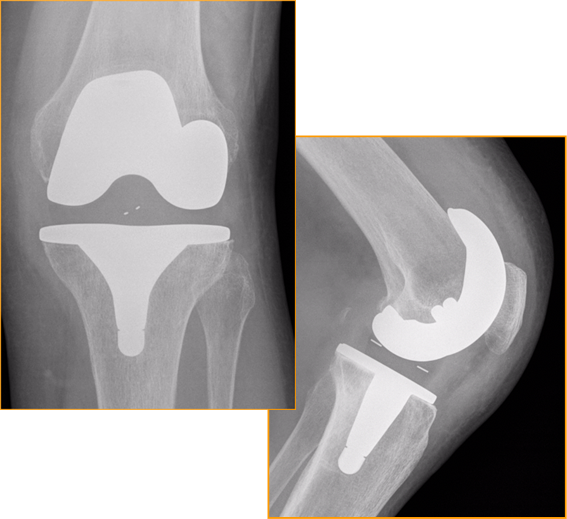

Below are the prostheses with links we commonly use but this is not exhaustive.